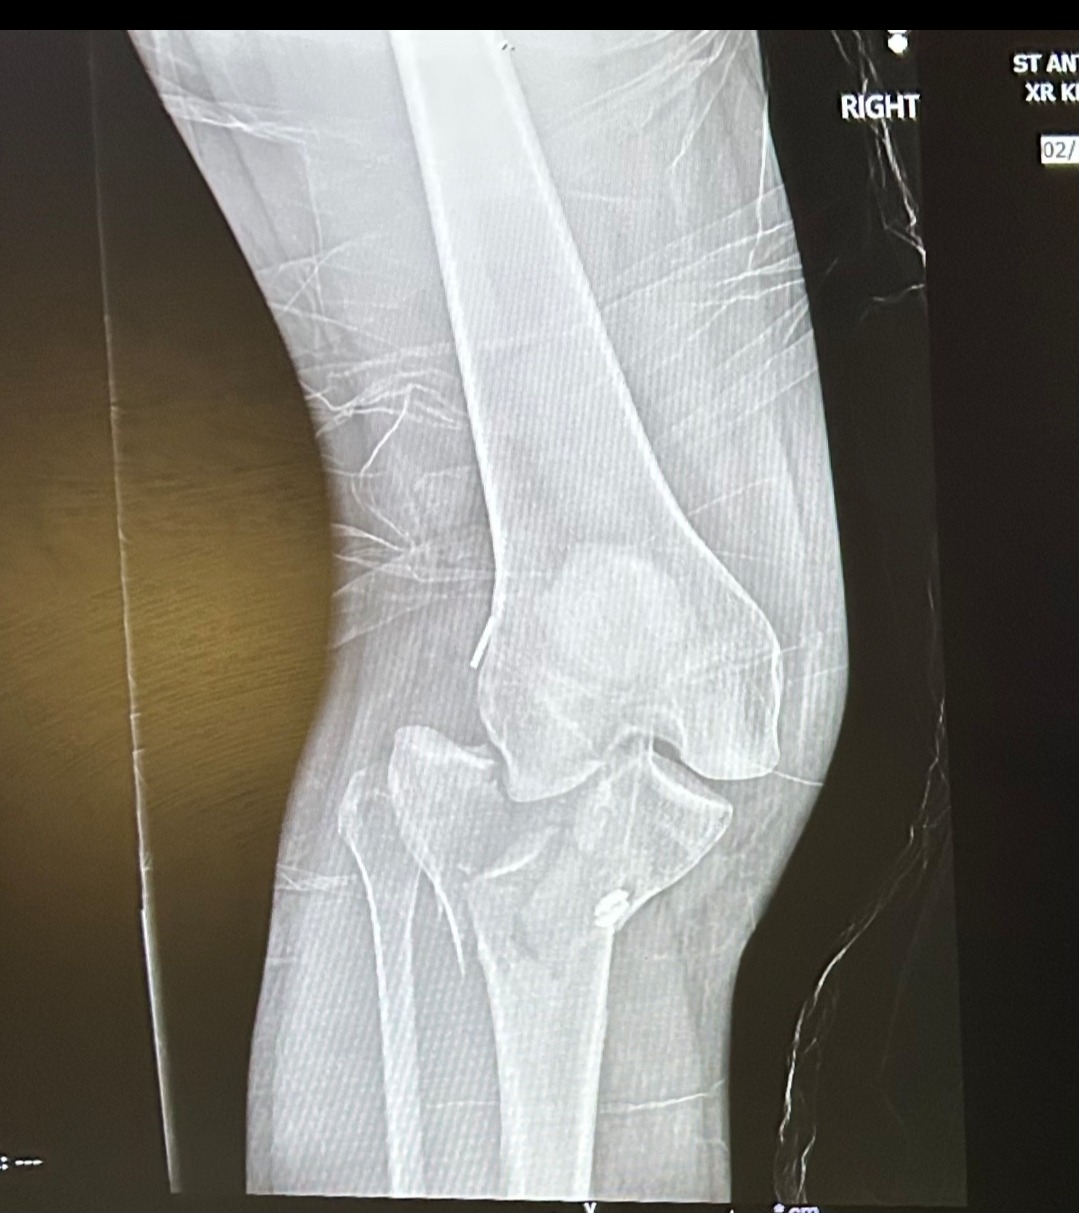

Earlier this year, Robin suffered a severe leg injury in a ski accident when she hit a rock hidden beneath the snow. The accident required multiple surgeries and a long, difficult recovery process. On top of that, she had already endured the heartbreaking loss of her boyfriend in a climbing accident last summer.